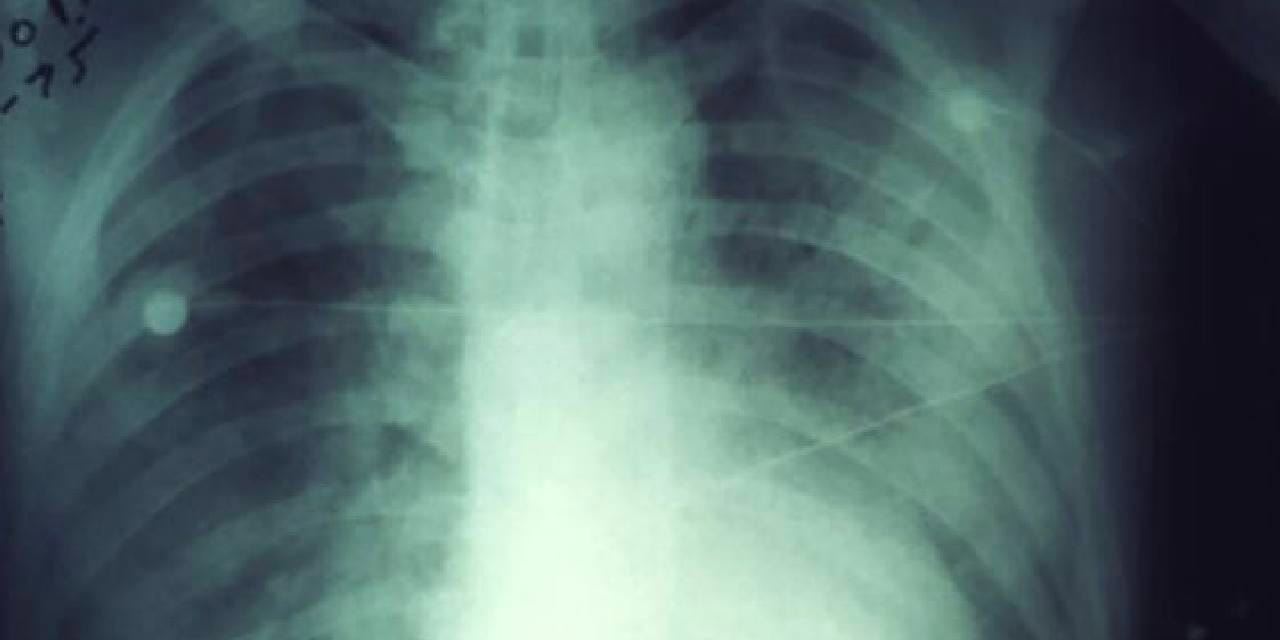

ABD’nin Arizona eyaletinde, 2007’den bu yana ilk kez bir kişi akciğer vebası nedeniyle hayatını kaybetti. Coconino bölgesi yetkilileri, internet sitesinden yaptıkları açıklamada, bir bölge sakininin akciğer vebası sonucu yaşamını yitirdiğini duyurdu.

Yetkililer, halk sağlığını koruma amacıyla durumu paylaştıklarını ancak yaşamını yitiren kişiye dair ayrıntılı bilgi vermeyeceklerini belirtti. Akciğer vebası, hızlı tedavi edilmediğinde ölümcül olabilen nadir bir enfeksiyon olarak biliniyor.